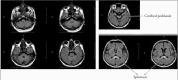

Figure 1

Axial fluid-attenuated inversion recovery (FLAIR) images show increased signal intensity in the regions of the medulla oblongata, posterior pons and posterior mesencephalon, bilateral dentate nuclei of cerebellum and splenium of the corpus callosum